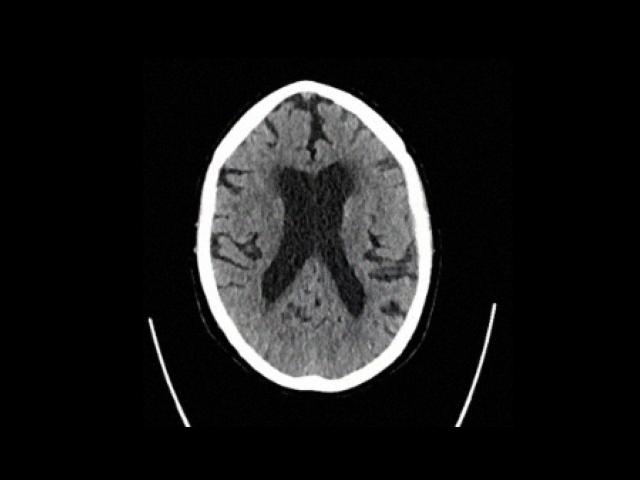

Sample Gallery